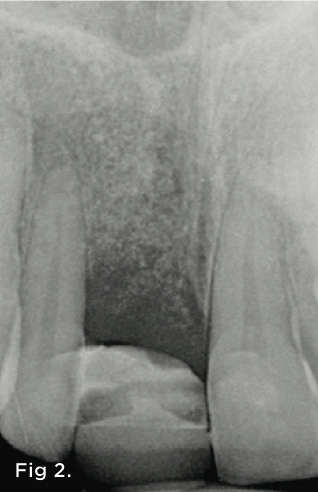

Fig 2. Radiograph showing the loss of periodontal attachment on the mesial aspect of tooth No. 7. A bone graft was placed when the implant was removed.

Figure 2